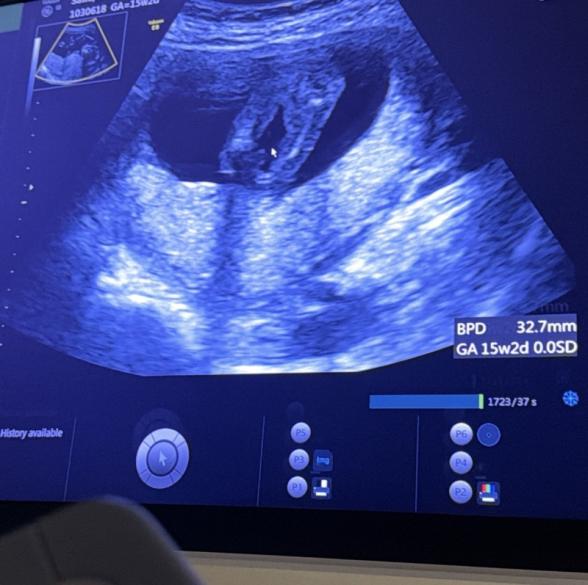

現在15w2dの妊婦です。 今回検診でおそらく女の子かなーと言われましたが 1つ目の写真は今お股になにもないように見えますが 2つ目の写真にはシンボルがついてるのかな?とも思います。 男女どちらの可能性が高いか、 今の時点での宮川先生の見解をお伺いしたいですm(_ _)m

エコー写真についてですね。

2枚目のお写真で、確かに足の間に何かありそうにも見えますね。

臍の緒の可能性もないかなと思いました。

また斜めに走る2本の白い線は、両足それぞれの内側の線にあたるのではないかとも思いました。

写している角度で、下側から見ている画像でもないかと思いました。

女の子可能性は高そうに思いましたが、また次回の健診の際にかかりつけの先生にもご相談いただけたらと思います。